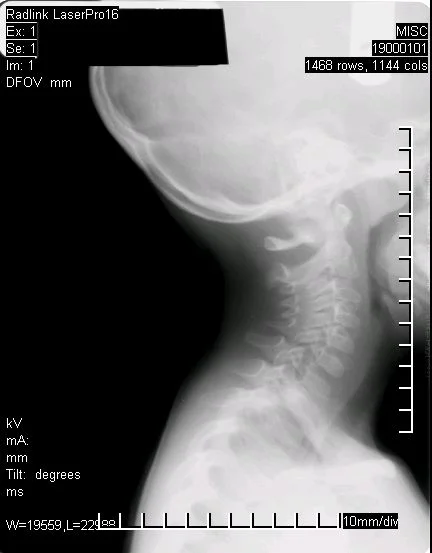

After Corrective Care (manual short term adjusting)